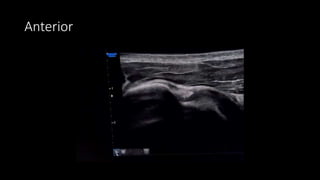

Anterior Region

Scanning Protocol

• Patient seated in upright position

• Shoulder In neutral and adducted

• Elbow flexed 90 degrees, forearm and hand

supinated and resting on the ipsilateral thigh

• Scan LHBT transverse and longitudinally

• Internally and externally rotate the arm to assess

for possible biceps tendon subluxation

• Subscapularis tendon best viewed with the

shoulder in external rotation